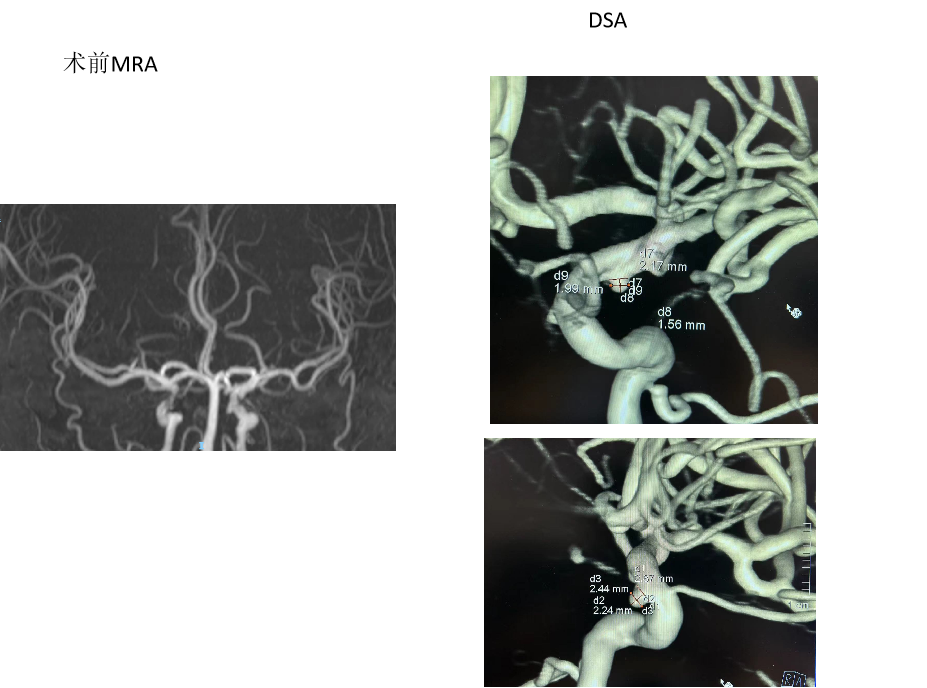

外院DSA:左侧颈内动脉C7段动脉瘤

造影检查,备颅内动脉瘤栓塞术+nuva 密网支架植入

选择TJED5.0-18(4.5x27),泰杰18微导管,支架输送费劲,维持张力释放自膨好,没有疝入动脉瘤,支撑力好;转弯处稍减张释放,支架尾端没打开;推拉支架导丝,尾端打开;过管顺利,填圈。

术后即刻DSA

支架:Nuva血流导向密网支架TJED-D-5.0-18(4.5x27)

2023-05-12 术后CT

因“突发头痛、呕吐6天”于2023-05-8 12:45 急诊平车入院。神经系统:神志清,精神差,言语流利,双侧额纹对称,双侧瞳孔等大等圆,直径约2.5mm,对光反射灵敏,双侧鼻唇沟对称,口角无歪斜,伸舌居中,颈软无抵抗,四肢肢体肌力检查不配合,肌张力正常,生理反射存在,病理反射未引出。

当地医院头部CT:SAH

初步诊断:1、颅内动脉瘤 2、蛛网膜下腔出血

2023-05-8 手术

外院首次CT影像片未带,我院复查头部CT,右侧积血较多,故优先处理右侧动脉瘤,尝试裸栓;但左侧颈眼动脉瘤形态不规则,也有可能是责任动脉瘤,拟过几日再支架辅助栓塞。

2023-05-8 手术

2023-05-10 术后CT

Nuva 4.0x24,非常顺滑到位,稍维持张力,自主打开好;半释放保护瘤颈,填入泰杰3d36、Axium2d24、1.5x4;微导丝按摩支架。

支架:Nuva血流导向密网支架TJED-D-4.5-18

一般项目:男,57,因“检查发现颅内动脉瘤6年”于2023-5-8 入院。

病例特点:患者诉6年前因头晕至广西医科大学一附院行头部CTA检查发现颅内动脉瘤,未予以处理。

既往史:2014年因蛛网膜下腔出血在南宁红会医院住院,具体治疗不详。

NS(-) 。

辅查:2017年广西医科大学一附院头部CTA提示左侧椎动脉V4段动脉瘤。

诊疗计划

nuva 密网支架植入

TJED-D-5.0-35(4.5x49),XT27输送很涩,释放过程控制好张力支架还是不断回缩,考虑直径过小,维持微导管较大张力释放,收尾稍减张释放,支架打开好。

动脉瘤内造影剂滞留

支架:Nuva密网支架TJED-D-5.0-35(4.5x49)

术后第一天

一般项目:姓名:闫月君 性别:女 年龄:64,因“右侧颈内动脉动脉瘤栓塞后半年”于2023-5-15 11:59 非急诊入院。

患者自诉半年前在广西壮族自治区人民医院桃源区行右侧颈内动脉C6动脉瘤血流导向密网支架(Pipeline)植入术,术后病情好转出院,现为复查造影入院。

诊断:1、左侧颈内动脉C6段动脉瘤 2、右侧颈内动脉C6段动脉瘤血流导向密网支架植入术后

首次RICA An ped支架植入,瘤内造影剂明显滞留。

诊疗计划

造影检查,备nuva 密网支架植入治疗残留动脉瘤或左侧C6段动脉瘤

2023-5-19手术

右侧ICA造影:动脉瘤正处于继续愈合状态,无需再处理

左侧C6多发动脉瘤

支架:泰杰Nuva密网支架TJED-4.5-16,

术后第一天

男,60岁,因“反复头痛10余年”于2016-05-16 16:14 非急诊步行入院。

2023-5-8 MRI+MRA+DWI:右侧颈内动脉C6段中-重度狭窄,右侧大脑后动脉P3段局部管腔轻度狭窄。考虑左侧颈内动脉C4、C6段动脉瘤。

初步诊断:1.左侧颈内动脉C4、C6段动脉瘤

2.右侧颈内动脉C6段中-重度狭窄

3.右侧大脑后动脉P3段局部轻度狭窄

造影检查,备颅内动脉瘤栓塞术+nuva 密网支架植入

其他:Nuva TJED-4.5-25、心凯诺颅内球囊扩张导管 4.0*15mm